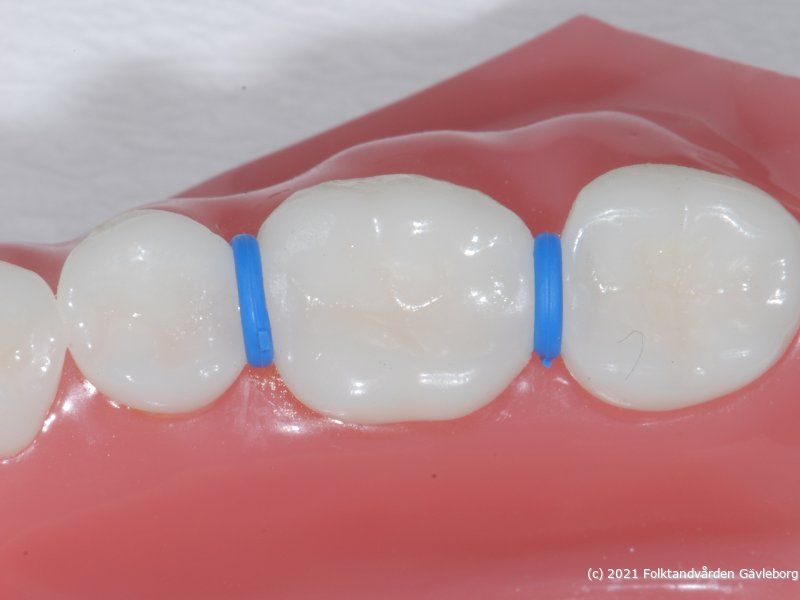

På ortodontiklinikerna diagnostiserar och behandlar vi bettfel på både barn och vuxna. Alla våra patienter kommer på remiss till oss. Vi behandlar bettfelen med fastsittande och avtagbar apparatur. Hos oss behandlas också de patienter som har avvikelser i käk- och ansiktsskelettet och som kräver tandreglering inför rekonstruktiv kirurgi. Vi har ett nära samarbete med allmäntandvård, privattandvård och övrig specialisttandvård i länet samt ett gott samarbete med Akademiska Sjukhuset i Uppsala när det gäller barn med olika syndrom och läpp-käk-gomdefekter. Våra specialistkliniker finns i Gävle och Hudiksvall.

Här nedan hittar du några exempel på vanligt förkommande behandlingar. Hittar du inget som passar det du vill visa, gå in på menyn ovan genom att föra musen över "Information". Navigera sedan till respektive apparatur. Klickar du på rubriken "Visa alla bilder" får du upp samtliga apparaturer som finns här.